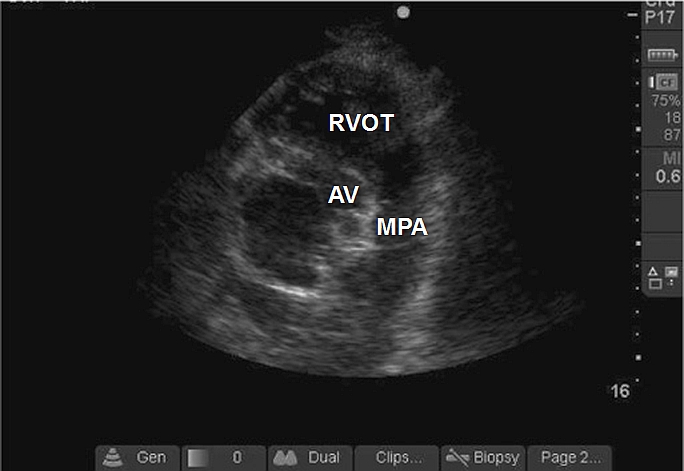

Case 7-7. Parasternal Short-axis View at Aortic Valve Level

Video 7-7A. The aortic valve (AV), the tricuspid valve (TV), and the pulmonic valve (PV) in the parasternal short-axis AV view. The AV has three leaflets, which are morphologically normal.

Video 7-7B. This video shows no evidence of AV regurgitation with color Doppler.

Video 7-7C. Mild tricuspid regurgitation (TR) with color Doppler, but the jet appears truncated. The TR velocity gradient would be measured at this site as matter of routine, but several other views would be required before any conclusion could be made concerning the severity of the TR or the velocity gradient.

Video 7-7D. Mild pulmonic regurgitation with a regurgitant jet that is well positioned for Doppler interrogation, in order to estimate pulmonary artery diastolic pressure.

Video 7-7E. The main pulmonary artery (MPA). It is difficult to obtain this view in adult patients, but if obtained, it can be used for Doppler interrogation of MPA outflow, to measure PA diameter (enlarged in this case), and occasionally to identify pulmonary emboli.